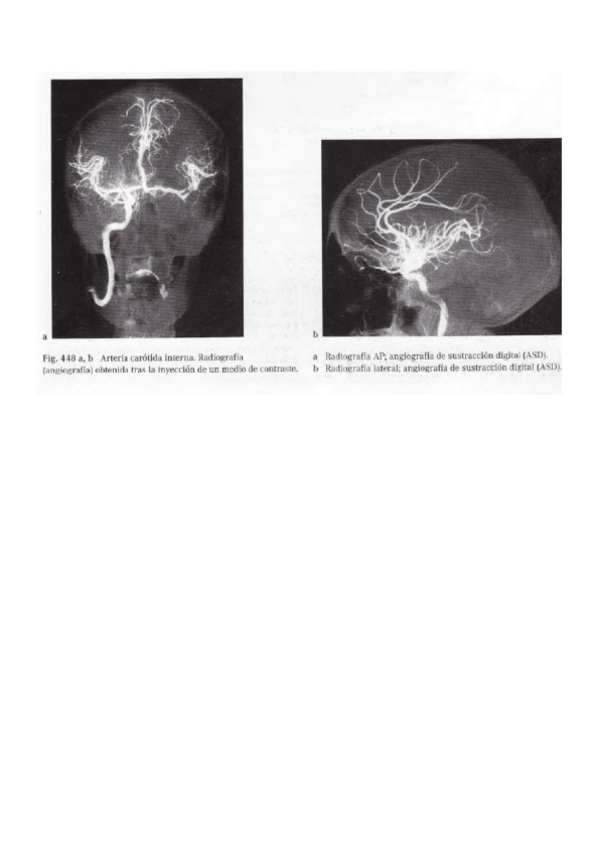

Angiografia-arteria-carotida.pdf